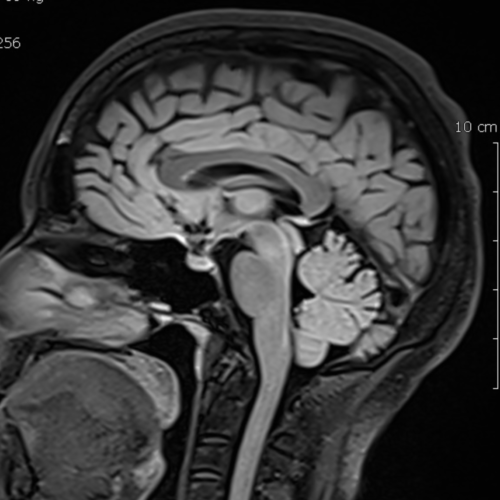

Cet examen est réalisé pour analyser le cerveau, le cervelet, l’hypophyse, les sinus, le polygone de Willis, les veines cérébrales. Il est réalisé en cas de céphalées, maux de têtes, troubles de la vision, déficit moteur ou neurologique.

Quels sont les résultats possibles d’une IRM encéphalique ?

Cette examen permets de diagnostiquer:

- les leucopathies classées Fazekas

- les tumeurs

- les anévrysmes

- les malformations vasculaires

- les anomalies ventriculaires

- les malformations cérébrales (ex Chiari)

- les AVC

- les hémorragies